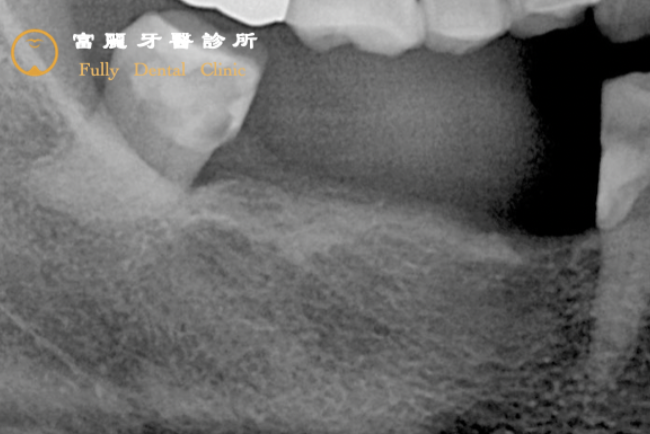

Before

牙根斷裂且包覆牙根的骨頭(灰色網狀)被細菌破壞(黑色的範圍),牙齒會開始出現晃動無法支撐咬合,尤其發生在對咬合功能十分重要的大臼齒,造成患者的咀嚼能力大大降低,因此決定以植牙來恢復!